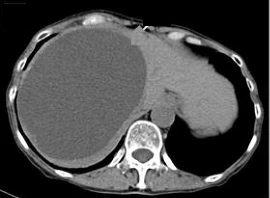

在 影像学检查中,肝囊肿可以是单发的,也可以是多发的,大小不一。单纯性肝囊肿的直径从不足 1 厘米到 30 厘米不等,且右肝叶更为常见【Marrero 2014 Bahirwani R 2008】。肝囊肿数量超过 20 个时,即被定义为多囊肝病(PLD)。单纯性肝囊肿通常容易与多囊肝病区分开来。

| 肝囊肿是先天性畸形,由胆管异常孤立形成,且不与胆道系统相通。肝囊肿通常无症状,在普通人群中患病率为 1% 至 5%,多在腹部影像学检查中偶然发现。1 单发的肝囊肿通常为单房性,伴有几个较小的囊肿,囊壁有上皮和分泌层,囊内为浆液性内容物。2 最常见的症状是腹痛,通常位于右上腹,疼痛程度不一,有时会因囊肿增大而加剧。